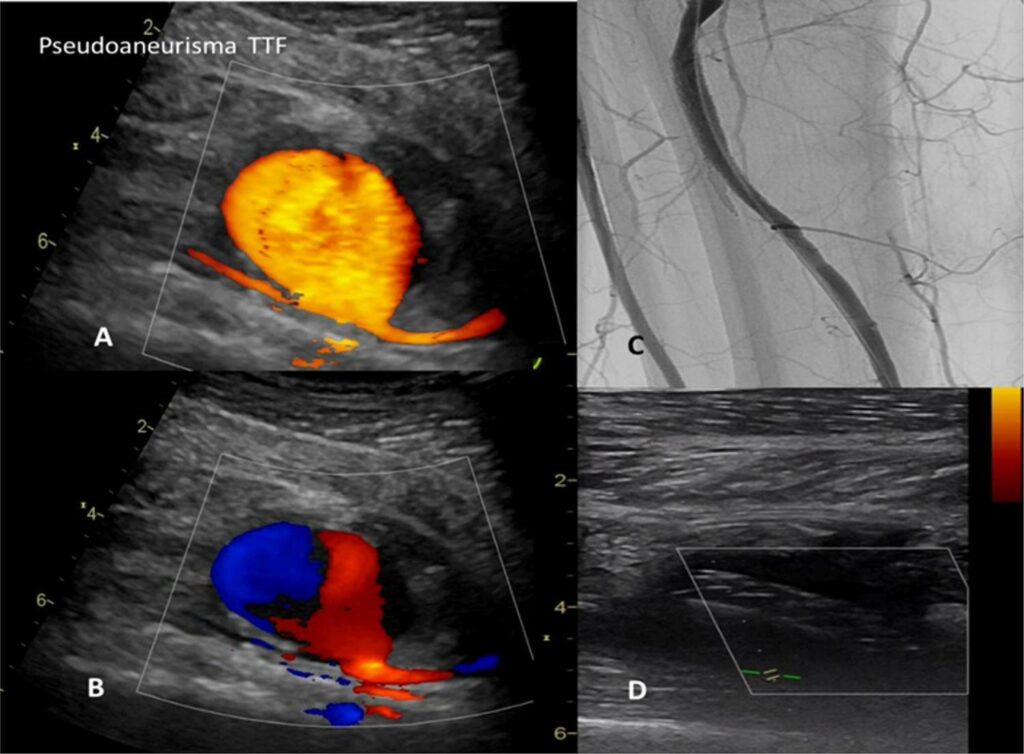

Doença de Behçet com Envolvimento Vascular: Relato de Caso

A doença de Behçet é uma síndrome inflamatória, multissistêmica, recidivante e de etiologia desconhecida. Envolve manifestações clínicas heterogêneas como: úlceras orais recidivantes, inflamação ocular, úlceras genitais e lesões de pele. Podem ocorrer manifestações mais graves por vasculite de pequenas e grandes artérias e/ou veias com formação de aneurismas arteriais ou trombose, além de envolvimento neurológico ou gastrintestinal. O diagnóstico é clínico e principalmente sintomático, e o tratamento pode incluir corticoides com ou sem imunossupressores e, eventualmente, outras intervenções para manifestações mais graves.